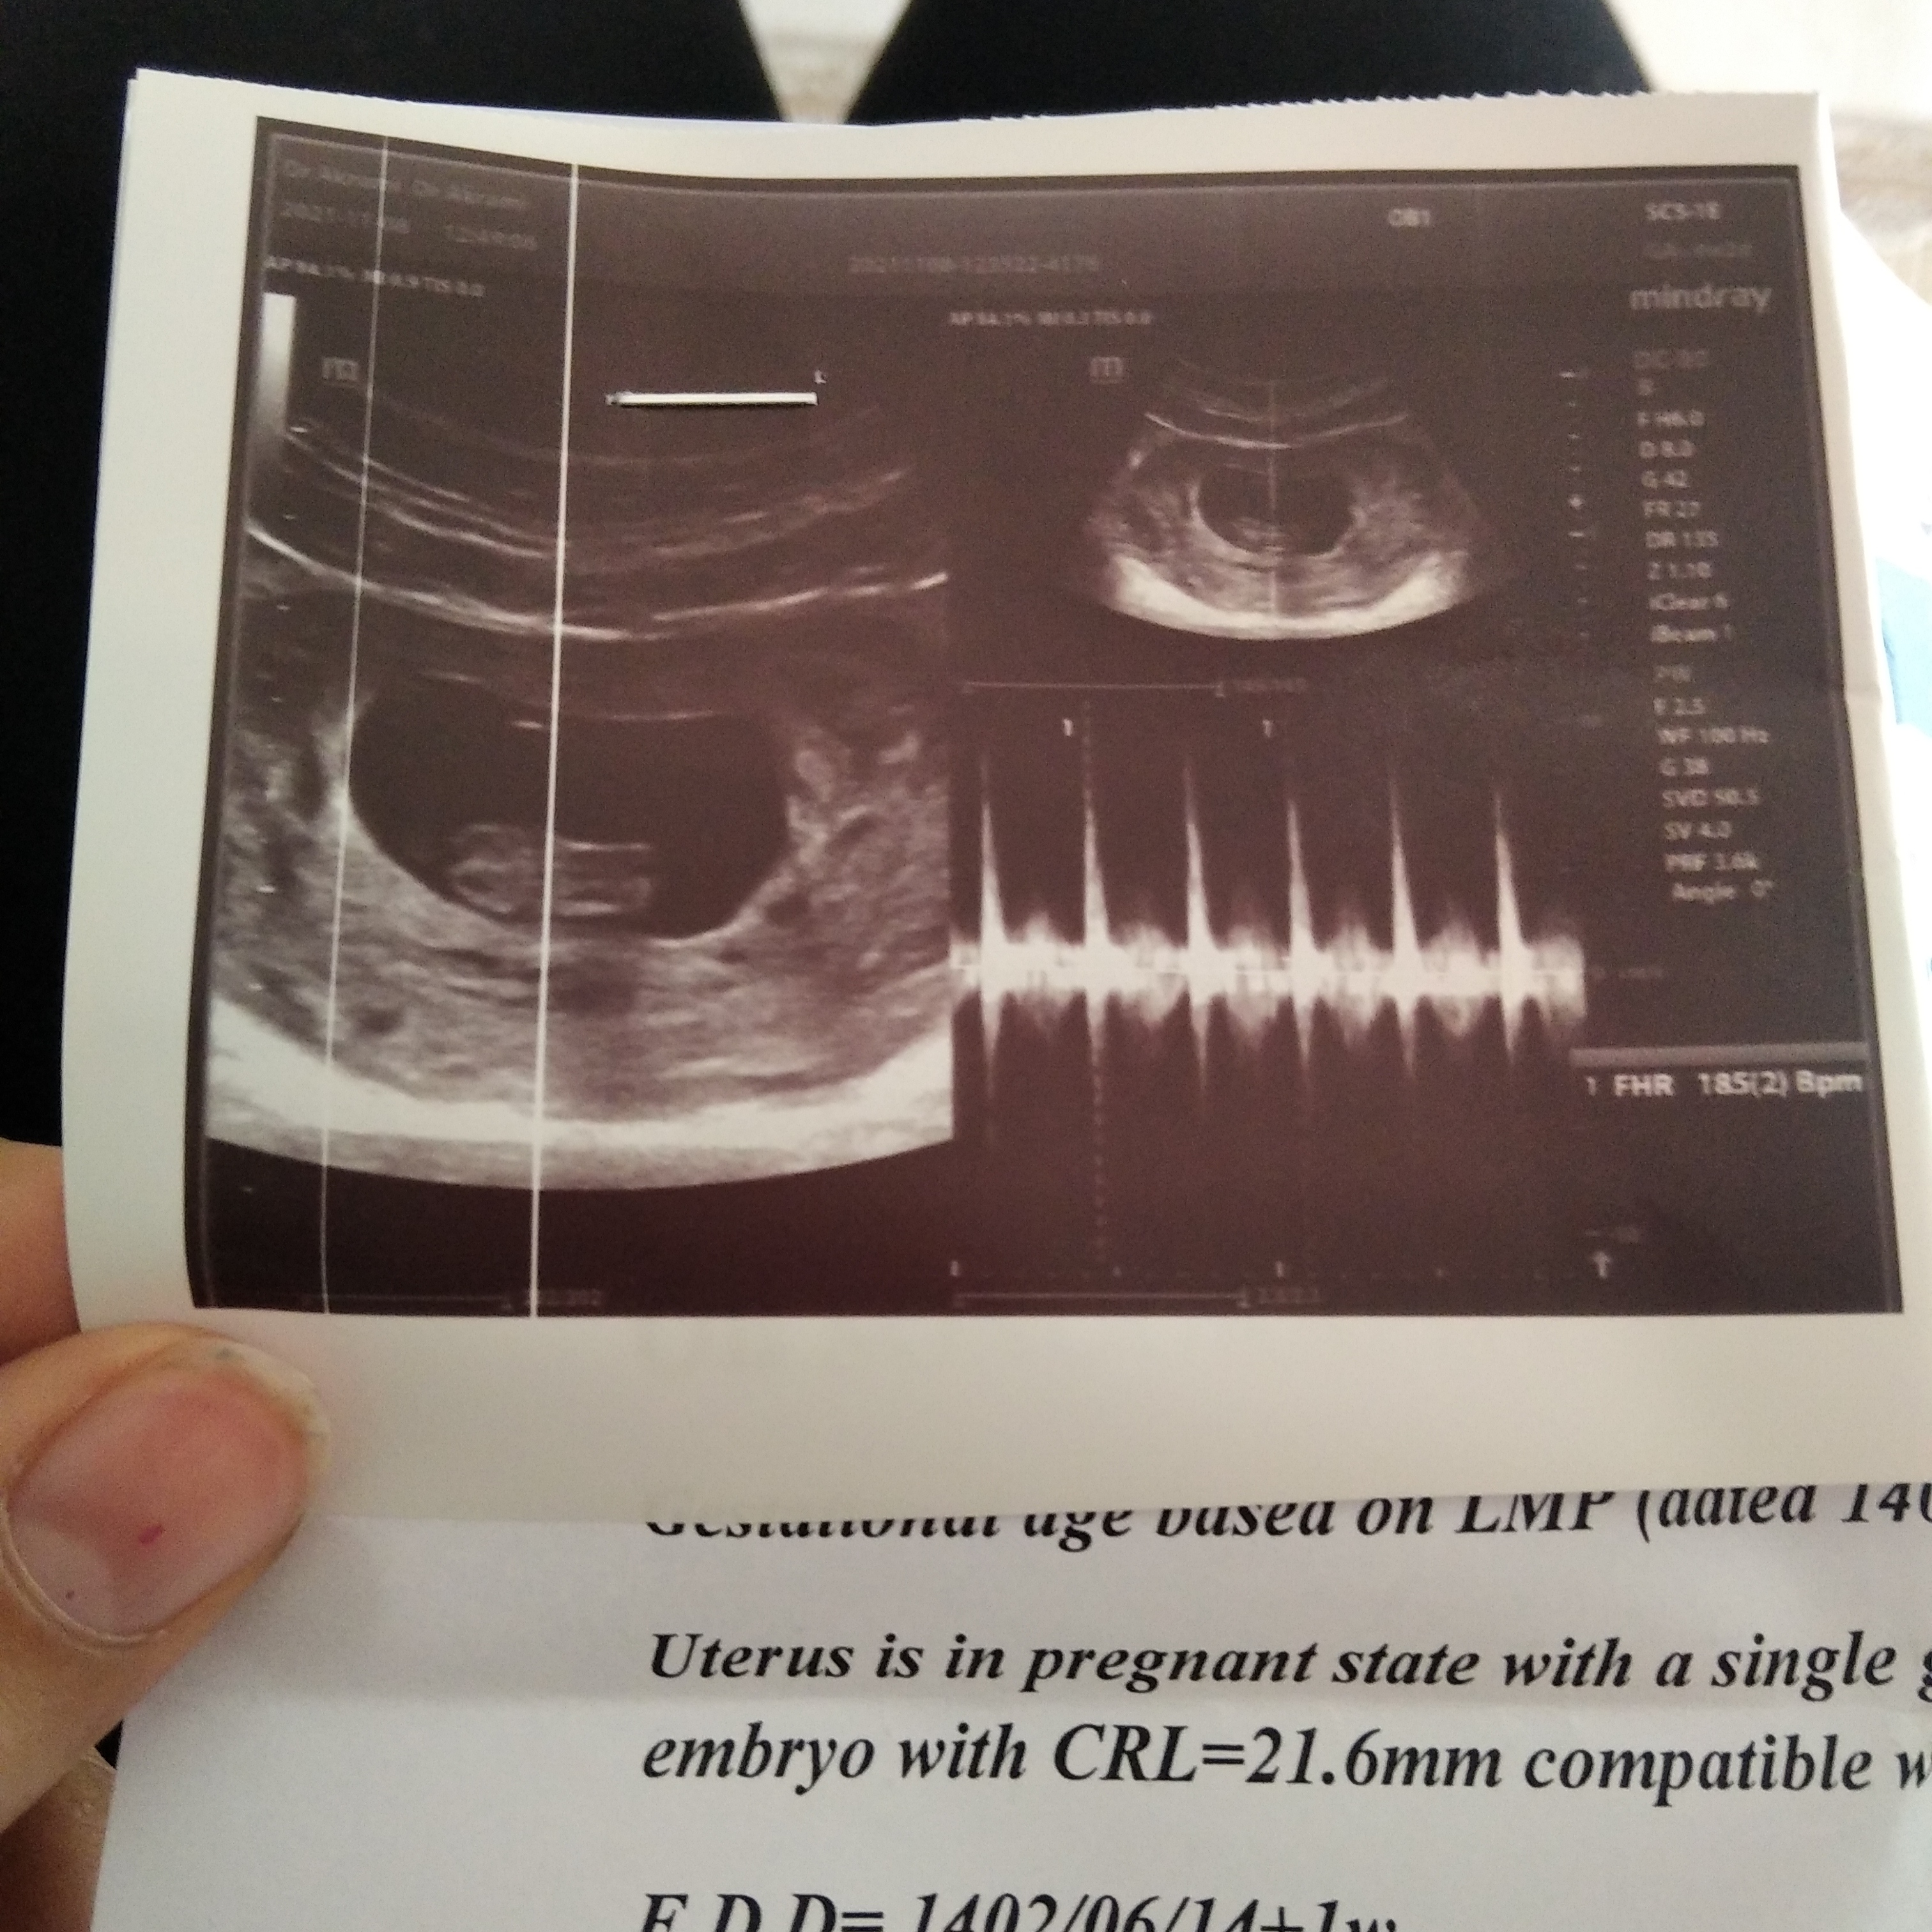

atiii73j مدیر استارتر عضویت: 1400/02/22 تعداد پست: 702 عنوان تعیین جنسیت 68 بازدید | 5 پست سلام دوستان کسی تعیین جنسیت از روی سونو قلب بلده؟ 1401/11/10 | 13:04 0 نفر لایک کرده اند ... گزارش تاپیک نامناسب